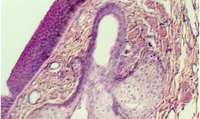

- Thick skin

- Thin skin

- Hair